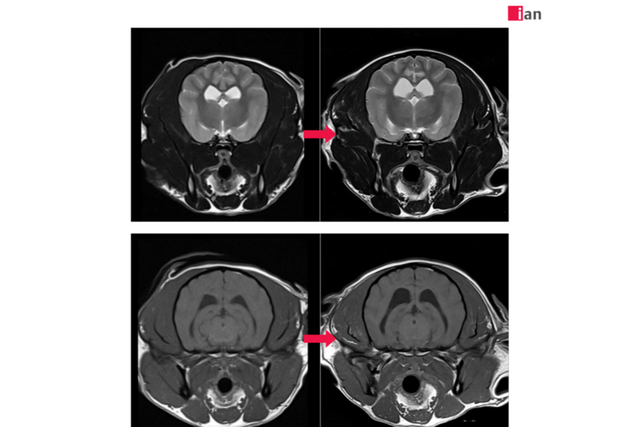

AI 도입 후 품질이 개선된 MRI 영상 사진. (사진=이안동물의학센터)

2023년 말 최첨단 AI MRI 소프트웨어를 도입한 이안동물의학센터는 촬영 시간 단축과 영상 품질 극대화라는 두 마리 토끼를 동시에 잡았다. 딥러닝 알고리즘을 통한 이미지 재구성과 노이즈 제거, 선명도 향상은 보다 신속하고 정확한 진단을 가능하게 했으며, 보호자와 반려동물 모두에게 높은 만족도를 제공하고 있다.